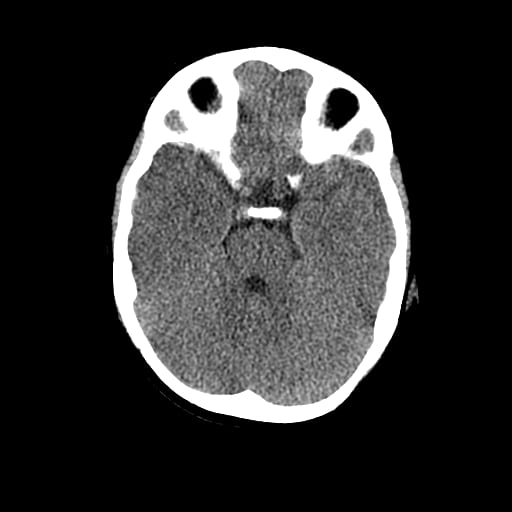

Age: 1

Sex: Male

Indication: Fall